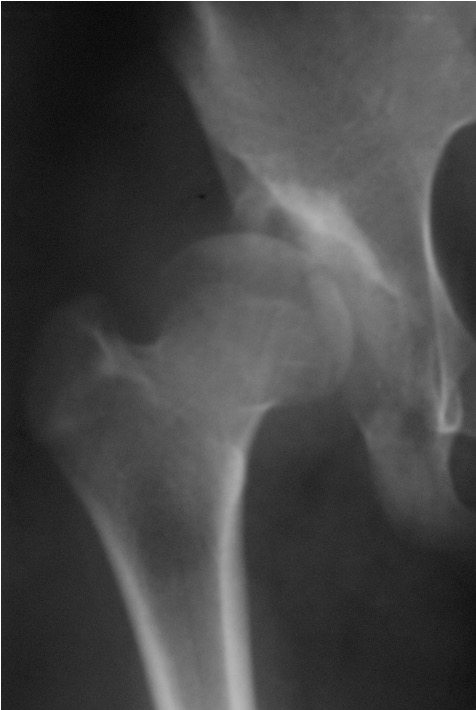

Femoral Varus Derotation Osteotomy (VDRO)

Indication

Tight reduction risking AVN

Unstable reduction with increased femoral anteversion

Increased femoral neck angle